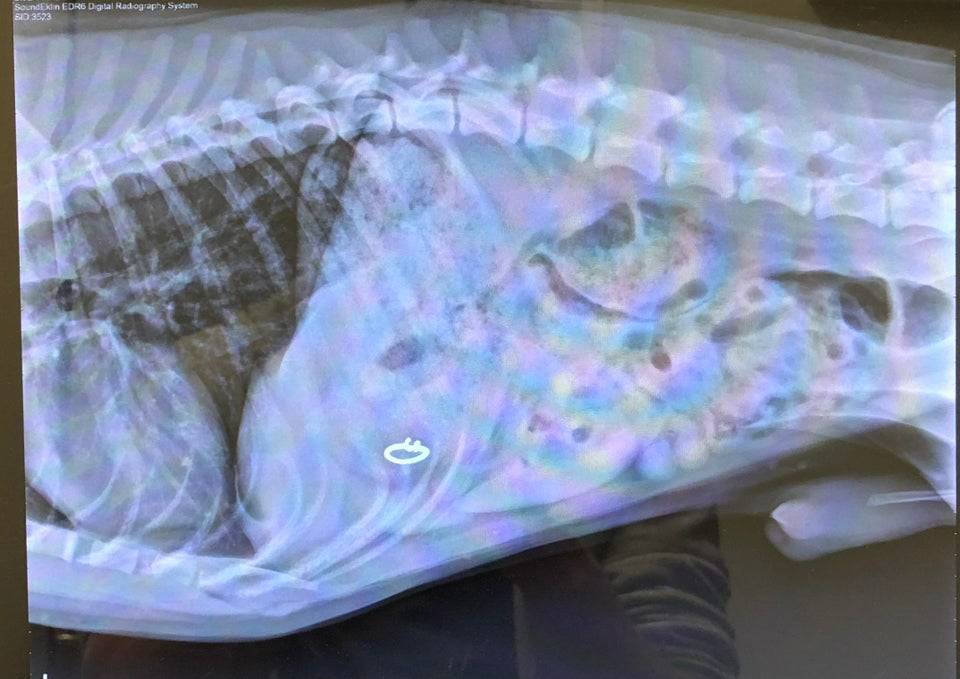

Wife’s Ring Came Up Missing

How did they know to get an X-ray for this issue? Did they conclude that she ate the ring?

That’s a wild conclusion to jump to, but how did she do it?